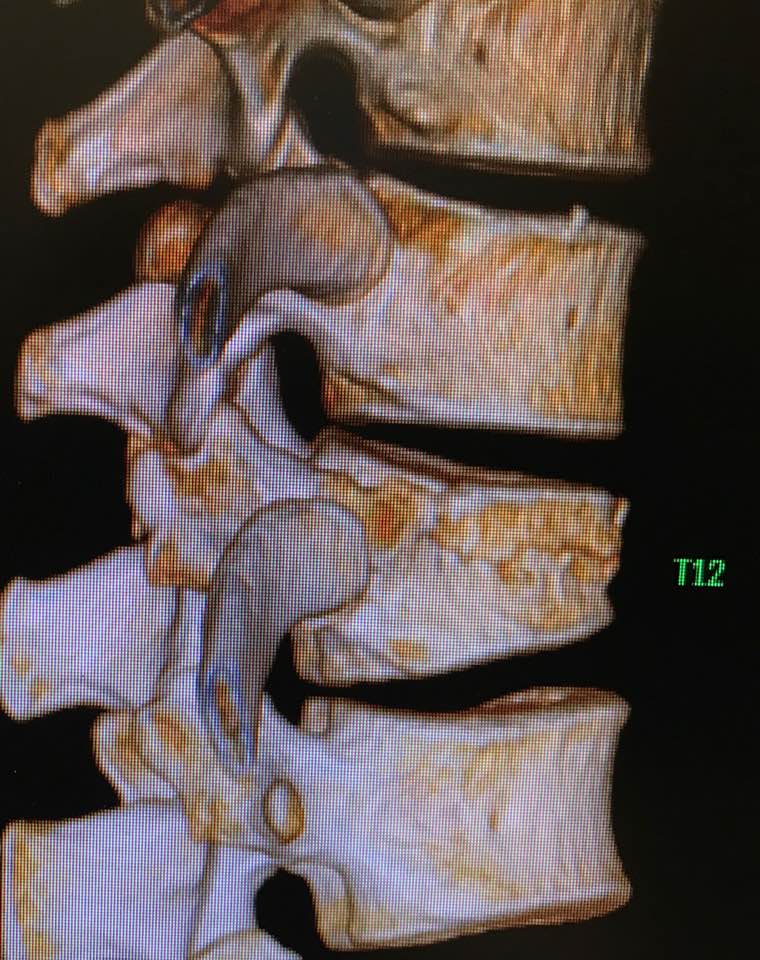

嚴重的工業意外受傷,T12胸脊椎不穩定的3段(前、中、後柱列)壓迫性脊柱椎體骨折

1. 即使您的胸部及胸脊椎柱被8英尺高和200磅重的巨大雪櫃嚴重壓碎, 您仍然生存, 您的中樞脊髓神經但沒有受到傷害.

2. 即使公立醫院忽畧了你不穩定的前、中、後3柱列的T12胸脊椎骨折,並在3天後容許你出院送回家, 你到私家醫院再進行第二次詳細檢查!

3. 幸運的是,入院前及兩天來你未有因為不穩定的脊柱椎體骨折碎片的移位而導致你脊髓中樞神經到不可逆轉和永久性的損傷致雙腿癱瘓及大小便失禁. 今天所有穩定你碎裂脊椎的手術都做完了.